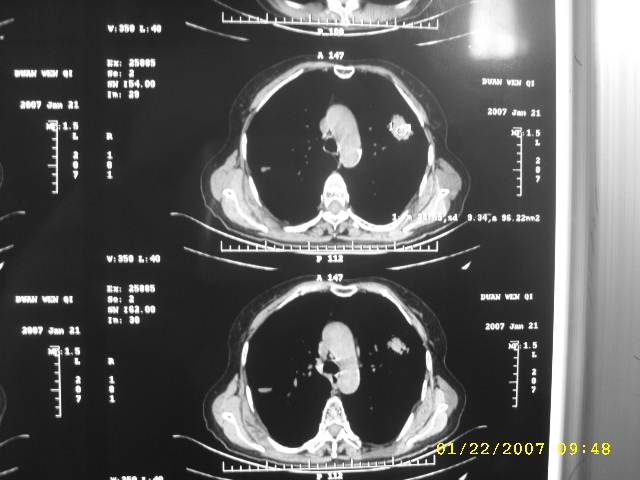

女,75.胸痛。

07.01.21.

1、周围型肺癌。2、慢性支气管炎、肺气肿、肺心病。

明显的不规则形肿块,分叶、短毛刺、胸膜刺激征,血管扭曲征等周围型肺癌的征象明显,应首先考虑周围型肺癌。应与肺多发结核球相鉴别

双侧肺内块状病灶,均见分叶毛刺,左肺见典型胸膜凹陷,双侧双原发癌.

1.双肺上叶及右肺下叶结节,周围散在卫星灶,接近4年的病史,纵隔无肿大淋巴结,考虑结核

2.桶状胸,慢支,肺气肿